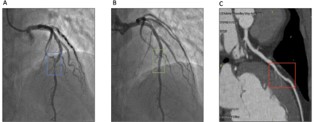

Coronary angiography demonstrated dynamic systolic compression of the mid-LAD with near-total narrowing in systole and resolution in diastole, consistent with MB (Figures 2A & 2B). No fixed stenosis or significant atherosclerotic plaques were identified in any vessel. CCTA was then performed to delineate anatomy. It demonstrated a 12 mm tunnelled segment in the mid-LAD with mild 50% luminal narrowing in diastole, without calcified or non-calcified plaques (Figure 2C). Such anatomical characterization has been shown to improve diagnostic yield compared with angiography alone [7,8].

Figure 2: Coronary angiogram and Coronary Computed Tomography Angiography (CCTA) showing mid-LAD myocardial bridging. (A) Still image of angiogram showing systolic compression of mid Left Anterior Descending (LAD) artery, highlighted in blue box; (B) Still image of angiogram in diastole, demonstrating no bridging in the similar segment, highlighted in green box; (C) CCTA showing intramyocardial course of mid LAD in diastole, highlighted in red.